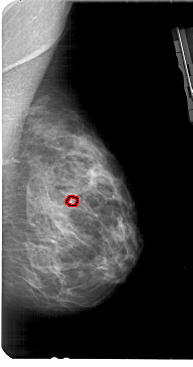

A_1949_1.RIGHT_MLO

RIGHT_MLO LINES 5491 PIXELS_PER_LINE 2881 BITS_PER_PIXEL 12 RESOLUTION 43.5 OVERLAY

FILE: A_1949_1.RIGHT_MLO.OVERLAY

TOTAL_ABNORMALITIES 1

ABNORMALITY 1

LESION_TYPE CALCIFICATION TYPE PLEOMORPHIC DISTRIBUTION CLUSTERED

ASSESSMENT 4

SUBTLETY 3

PATHOLOGY BENIGN

TOTAL_OUTLINES 1

BOUNDARY